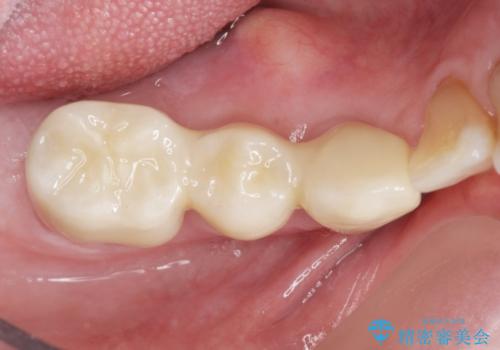

再生療法と骨外科処置により、歯周ポケットは全周2mm以下となりました。

奥歯の動揺がなくなりしっかりと咬むことができ、審美的・機能的にもご満足頂けました。

被せ物の種類:オールセラミッククラウン ベレッツァ